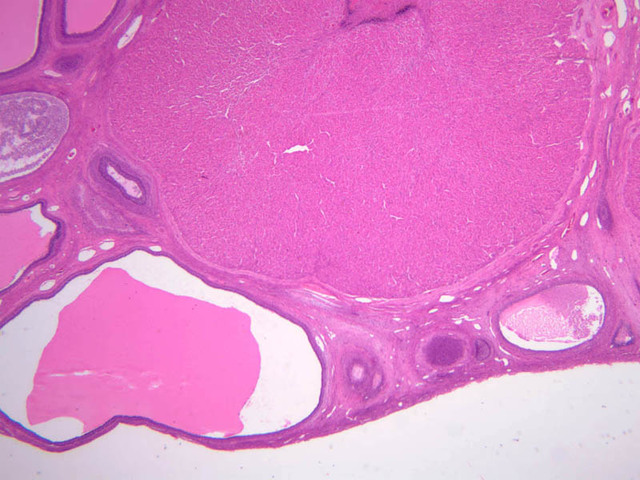

Corpus Albicans

The corpus luteum persists for 12 to 14 days. If fertilized ovum does not implant, the corpus luteum degenerates, leaving a scar which is referred to as the corpus albicans. This will also disappear eventually. Some of the B-54 slides in our collection have corpus albicans – try to identify a corpus albicans on your slide or consult with your neighbors. Corpus Albicans (some B-54 [1x-labeled] [2.5x] [1x-labeled, 2.5x, 10x])